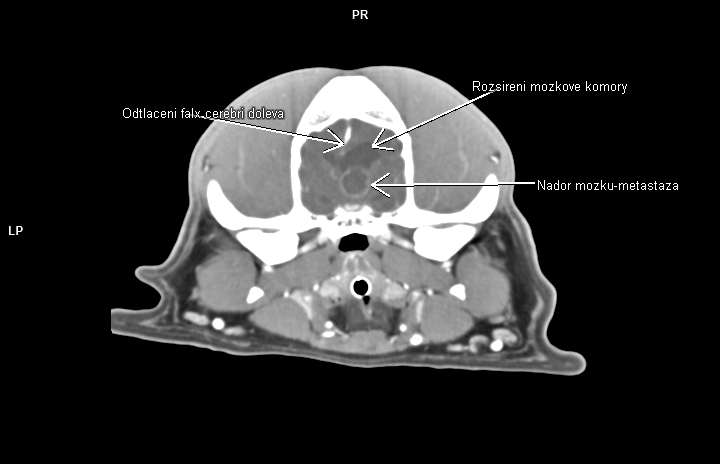

Nedílnou součástí diagnostiky ve veterinární onkologii se tak stává CT vyšetření. Velká spirální CT spolu s použitím kontrastní látky nám umožňují velmi detailní zobrazení i hlubokých struktur těla, stav okolních měkkých tkání, průběh velkých cév v bezprostředním okolí a přítomnost metastáz. Lze pak mnohem přesněji cíleně odebrat bioptické či cytologické vzorky z patologické tkáně, určit operabilnost nádoru a v případě nálezu metastatického rozsevu zvážit další postup (chemoterapie, ozařování atp.)

• primární a metastatické nádory mozku a mozkových plen,